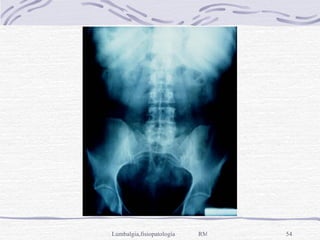

Diagnóstico Laboratorio: B.H., E.G.O., Q.S., perfil reumatológico Por imagen, Rx simple de columna lumbar AP, Lateral y Oblicua y Ap de Pelvis, con el paciente de pie y descalzo. TAC y RM en situaciones más específicas

Diagnóstico Laboratorio: B.H.,E.G.O., Q.S., perfil reumatológico Por imagen, Rx simple de columna lumbar AP, Lateral y Oblicua y Ap de Pelvis, con el paciente de pie y descalzo. TAC y RM en situaciones más específicas